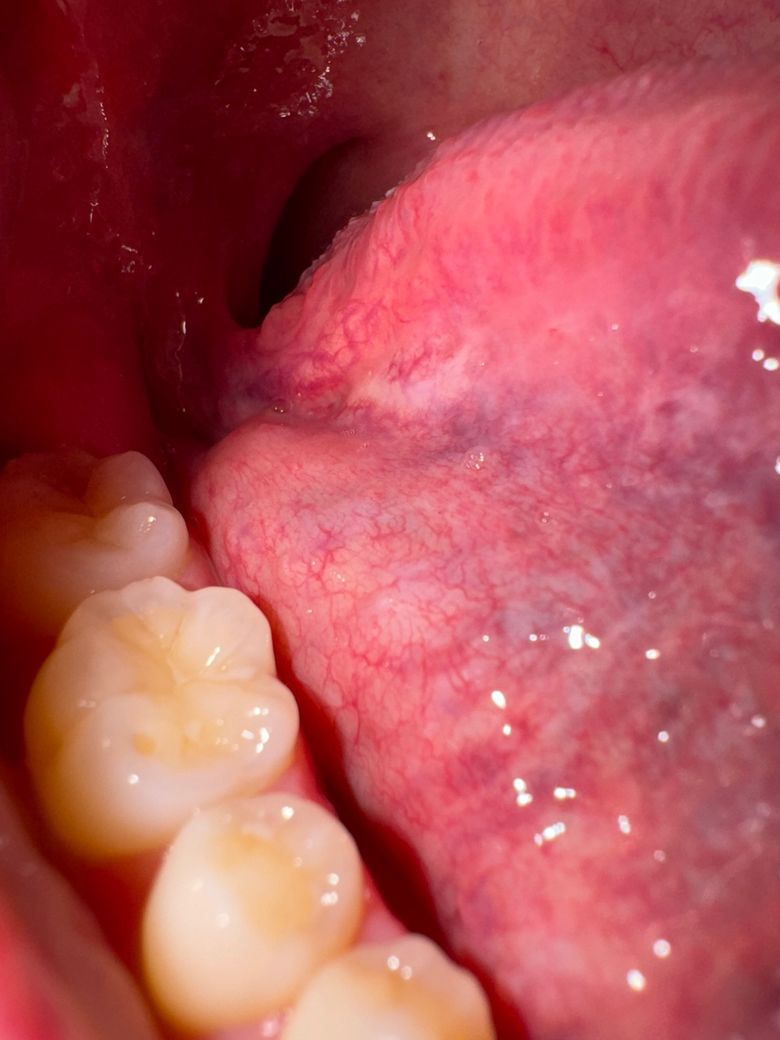

설암 초기증상인지 백반증인지 정상조직인지...ㅠㅠ

26세 남성입니다ㅠㅠ

아이코스 전자담배를 흡연하고있고

흡연한지는 7년째인데

백반증이나 설암 초기증상인건가요? ㅠㅠ

전혀 아프지도않고

우연히 혀 밑을 봤는데 사진들처럼 하얘져있어서 자꾸 신경쓰여서요ㅠㅠ

일단 일부 사진과 질문자님의 증상만으로 의견을 말씀드리자면, 약간의 덩어리가 하얗게 발생한 것으로 보이며 덩어리진 양상이 만져진다면 백반증일 가능성이 있어보이며, 설암의 경우 출혈이나 통증이 동반되는 경우가 많아 약간은 가능성이 떨어집니다.

다만 정확한 진단의 경우 치과에 가셔서 의사의 진찰 및 필요시 조직검사를 받으시는 것이 좋겠습니다.